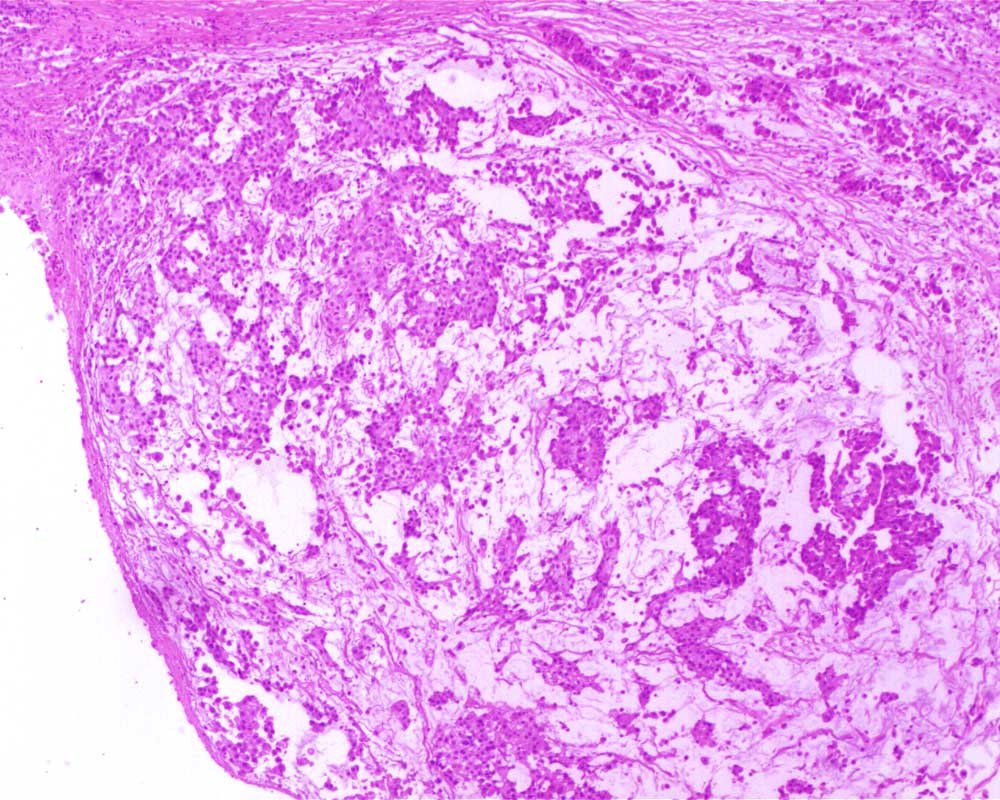

Case: PeritonealLesion

Final Diagnosis: